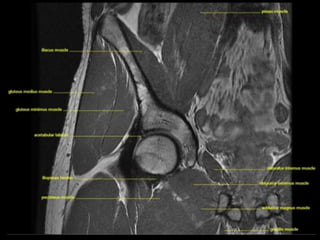

Hip Joint.